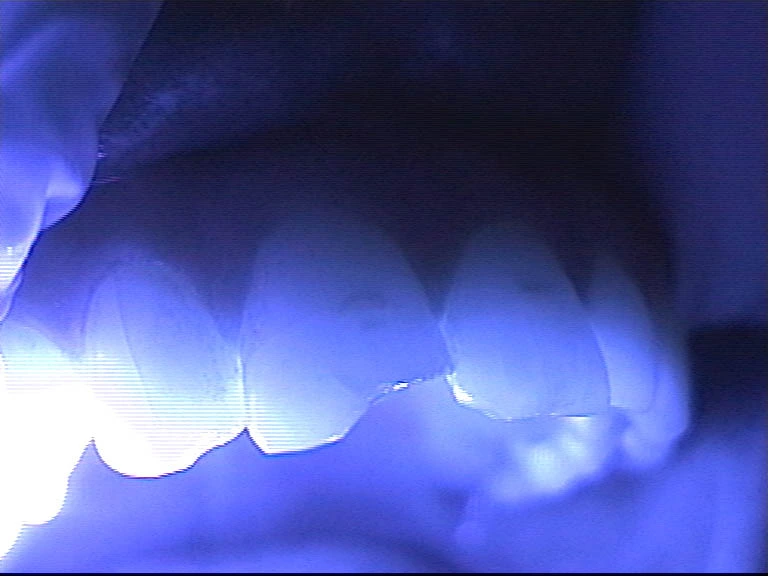

Mavi ışığa maruz kalan kompozit diş

dolgusunun nasıl sertleştiği

ve bazı pratik uygulama ipuçları.